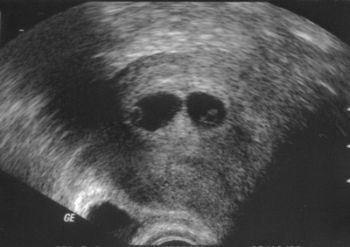

Beszkenneltük az UH-s képeket, úgyhogy íme a Bogyók (az első 7+4-en, a második 9+6-on, csak itt sajnos jól elbújtak, alig látszanak)

Kép